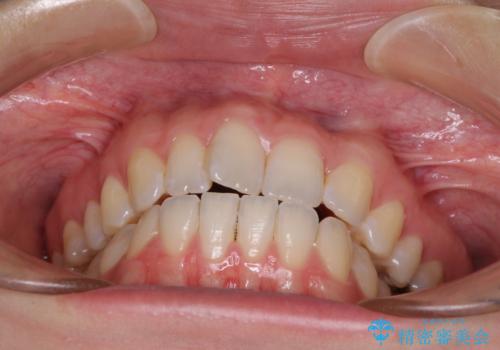

気になる上の歯を改善 インビザライン矯正

- 矯正治療の後戻りが気になるとのことで来院された患者様です。

上顎の後戻りをインビザライン・ライトで治療することとしました。

上顎のみの治療を希望されたため、咬み合わせをしっかりと改善することはできませんでしたが、審美面が大きく改善され、日常生活の機能面でも不具合を感じることはなく、大変満足していただきました。